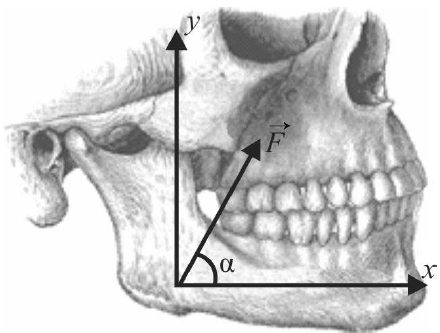

A mandíbula humana é capaz de realizar movimentos complexos e de aplicar forças de diferentes magnitudes, de acordo com as necessidades da mastigação.

mandíbula em estado de força

Considerando que há possibilidade de deslocamento da mandíbula, !$ \vec{d} !$ = (a, b), em que a e b são os deslocamentos nas direções x e y, respectivamente, e que o produto escalar entre os dois vetores !$ \vec{m} !$ = (mx, my) e !$ \vec{n} !$ = (nx, ny) é definido como !$ \vec{m} !$ . !$ \vec{n} !$= (mx nx + my ny), assinale a opção correta a respeito da força !$ \vec{F} !$ aplicada pela mandíbula representada na figura.